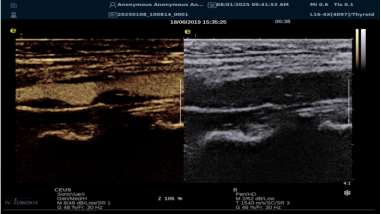

mFlowTM 超微血流显像技术

mFlowTM 超微血流技术在小型机器上率先实现微米级细小血管识别与低速血流捕捉,以往仅高端台式机具备此功能。该技术专注于颈动脉粥样硬化斑块内血流评估,无需造影剂,具有高分辨率、低运动伪像和高帧频成像特点。其优势如下:

image.png

? 运用 3D 壁滤波技术智能分析信号,可探测常规超声难以捕捉的低速血流,灵敏度高。

? 依据 Staub 标准对检查结果分级,直观展示斑块内新生血管血流,为斑块稳定性评估提供新指标。

? 基于多普勒原理,进行频谱测量并可进行VI指数测量,定量评估斑块内新生血管占比。

? 相较超声造影成像,无创便捷,为颈动脉易损斑块评估开辟新途径。